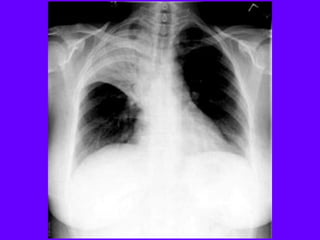

Bronchiectasis is defined as localized bronchial

Bronchiectasis Bronchiectasis is definedas localized bronchial dilatation. (signet-ring sign) bronchial wall thickening lack of normal tapering with visibility of airways in the peripheral lung mucus retention in the broncial lumen associated atelectasis and sometimes air trapping

ABPA: glove-fingershadow duetomucoid impaction in central bronchiectasisin a patientwith asthma.